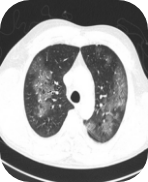

Chest computerised tomography (CT):

Bilateral ground glass opacities and a small

consolidation in the left lower lung lobe

Images supplied with permission of treating clinician.